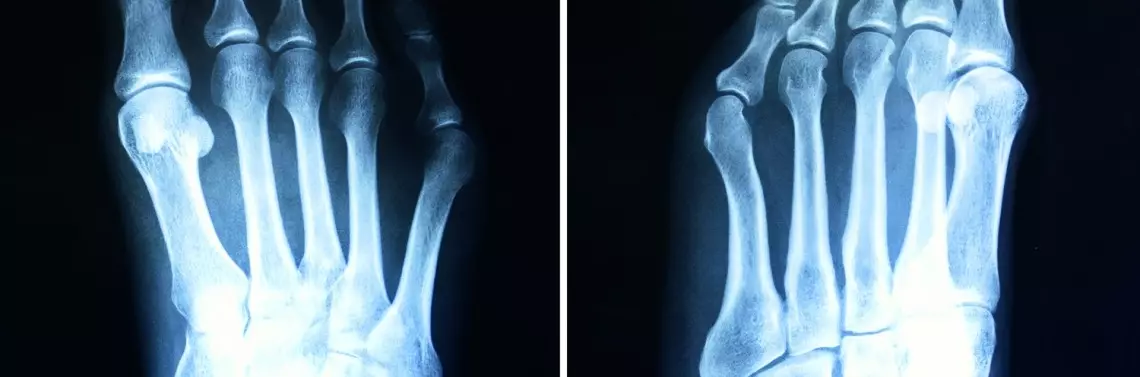

Haluks (hallux valgus) to koślawe zniekształcenie palucha w stawie I śródstopno-paliczkowym (metatarsophalangeal – MTP). Polega na koślawym ustawieniu palucha i szpotawym ustawieniu I kości śródstopia. Kąt pomiędzy osią palucha a osią I kości śródstopia przekracza 20°. Skutkiem tego jest uwydatnienie po stronie przyśrodkowej stopy głowy I kości śródstopia.